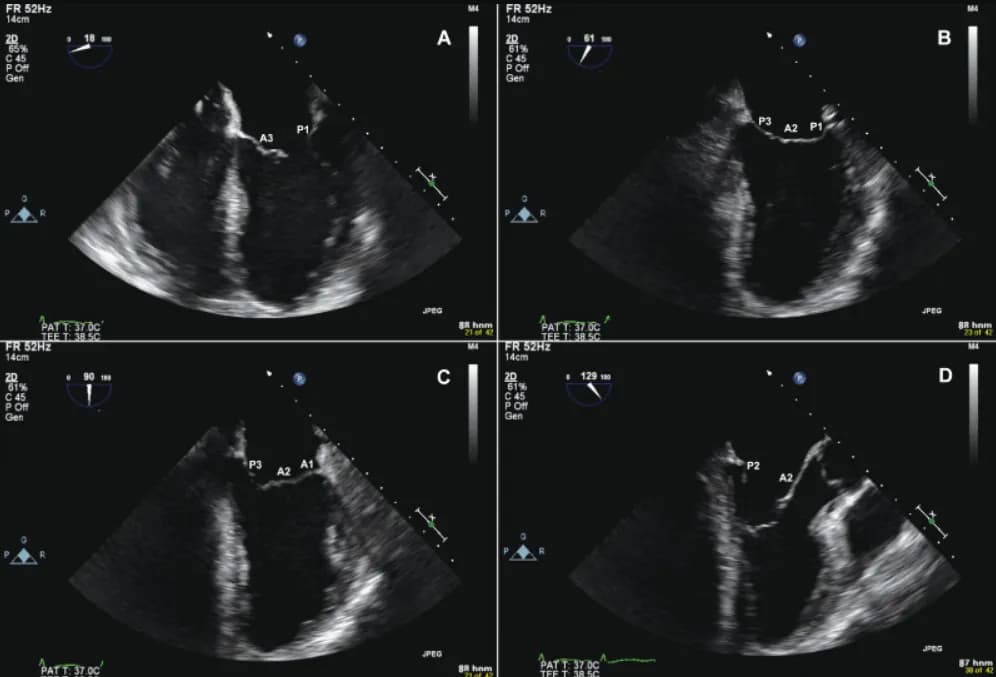

Vai trò của siêu âm trong đánh giá bệnh lý hẹp hở van tim

siêu âm timbệnh lý van timchức năng timhẹp hở van timtổn thương van

Siêu âm tim là phương pháp chẩn đoán sử dụng sóng âm để tạo ảnh tim, giúp bác sĩ quan sát chức năng tim và phát hiện bện...